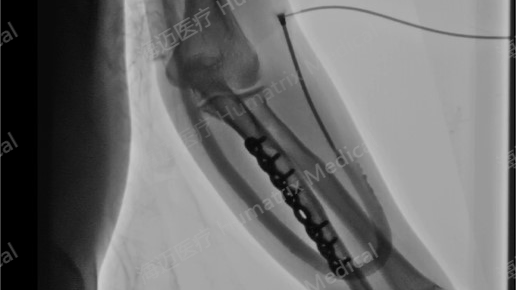

临床试验患者使用LineMatrix耐迈通®生物型人工血管长期血液透析,血管造影通畅